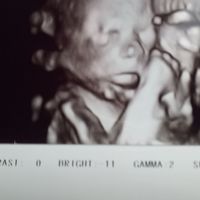

Ho paura a prenderlo ma sto troppo male vomito di continuo e sono a casa da 20 giorni non riesco piu a fare nulla mi viene da piangere help ππ